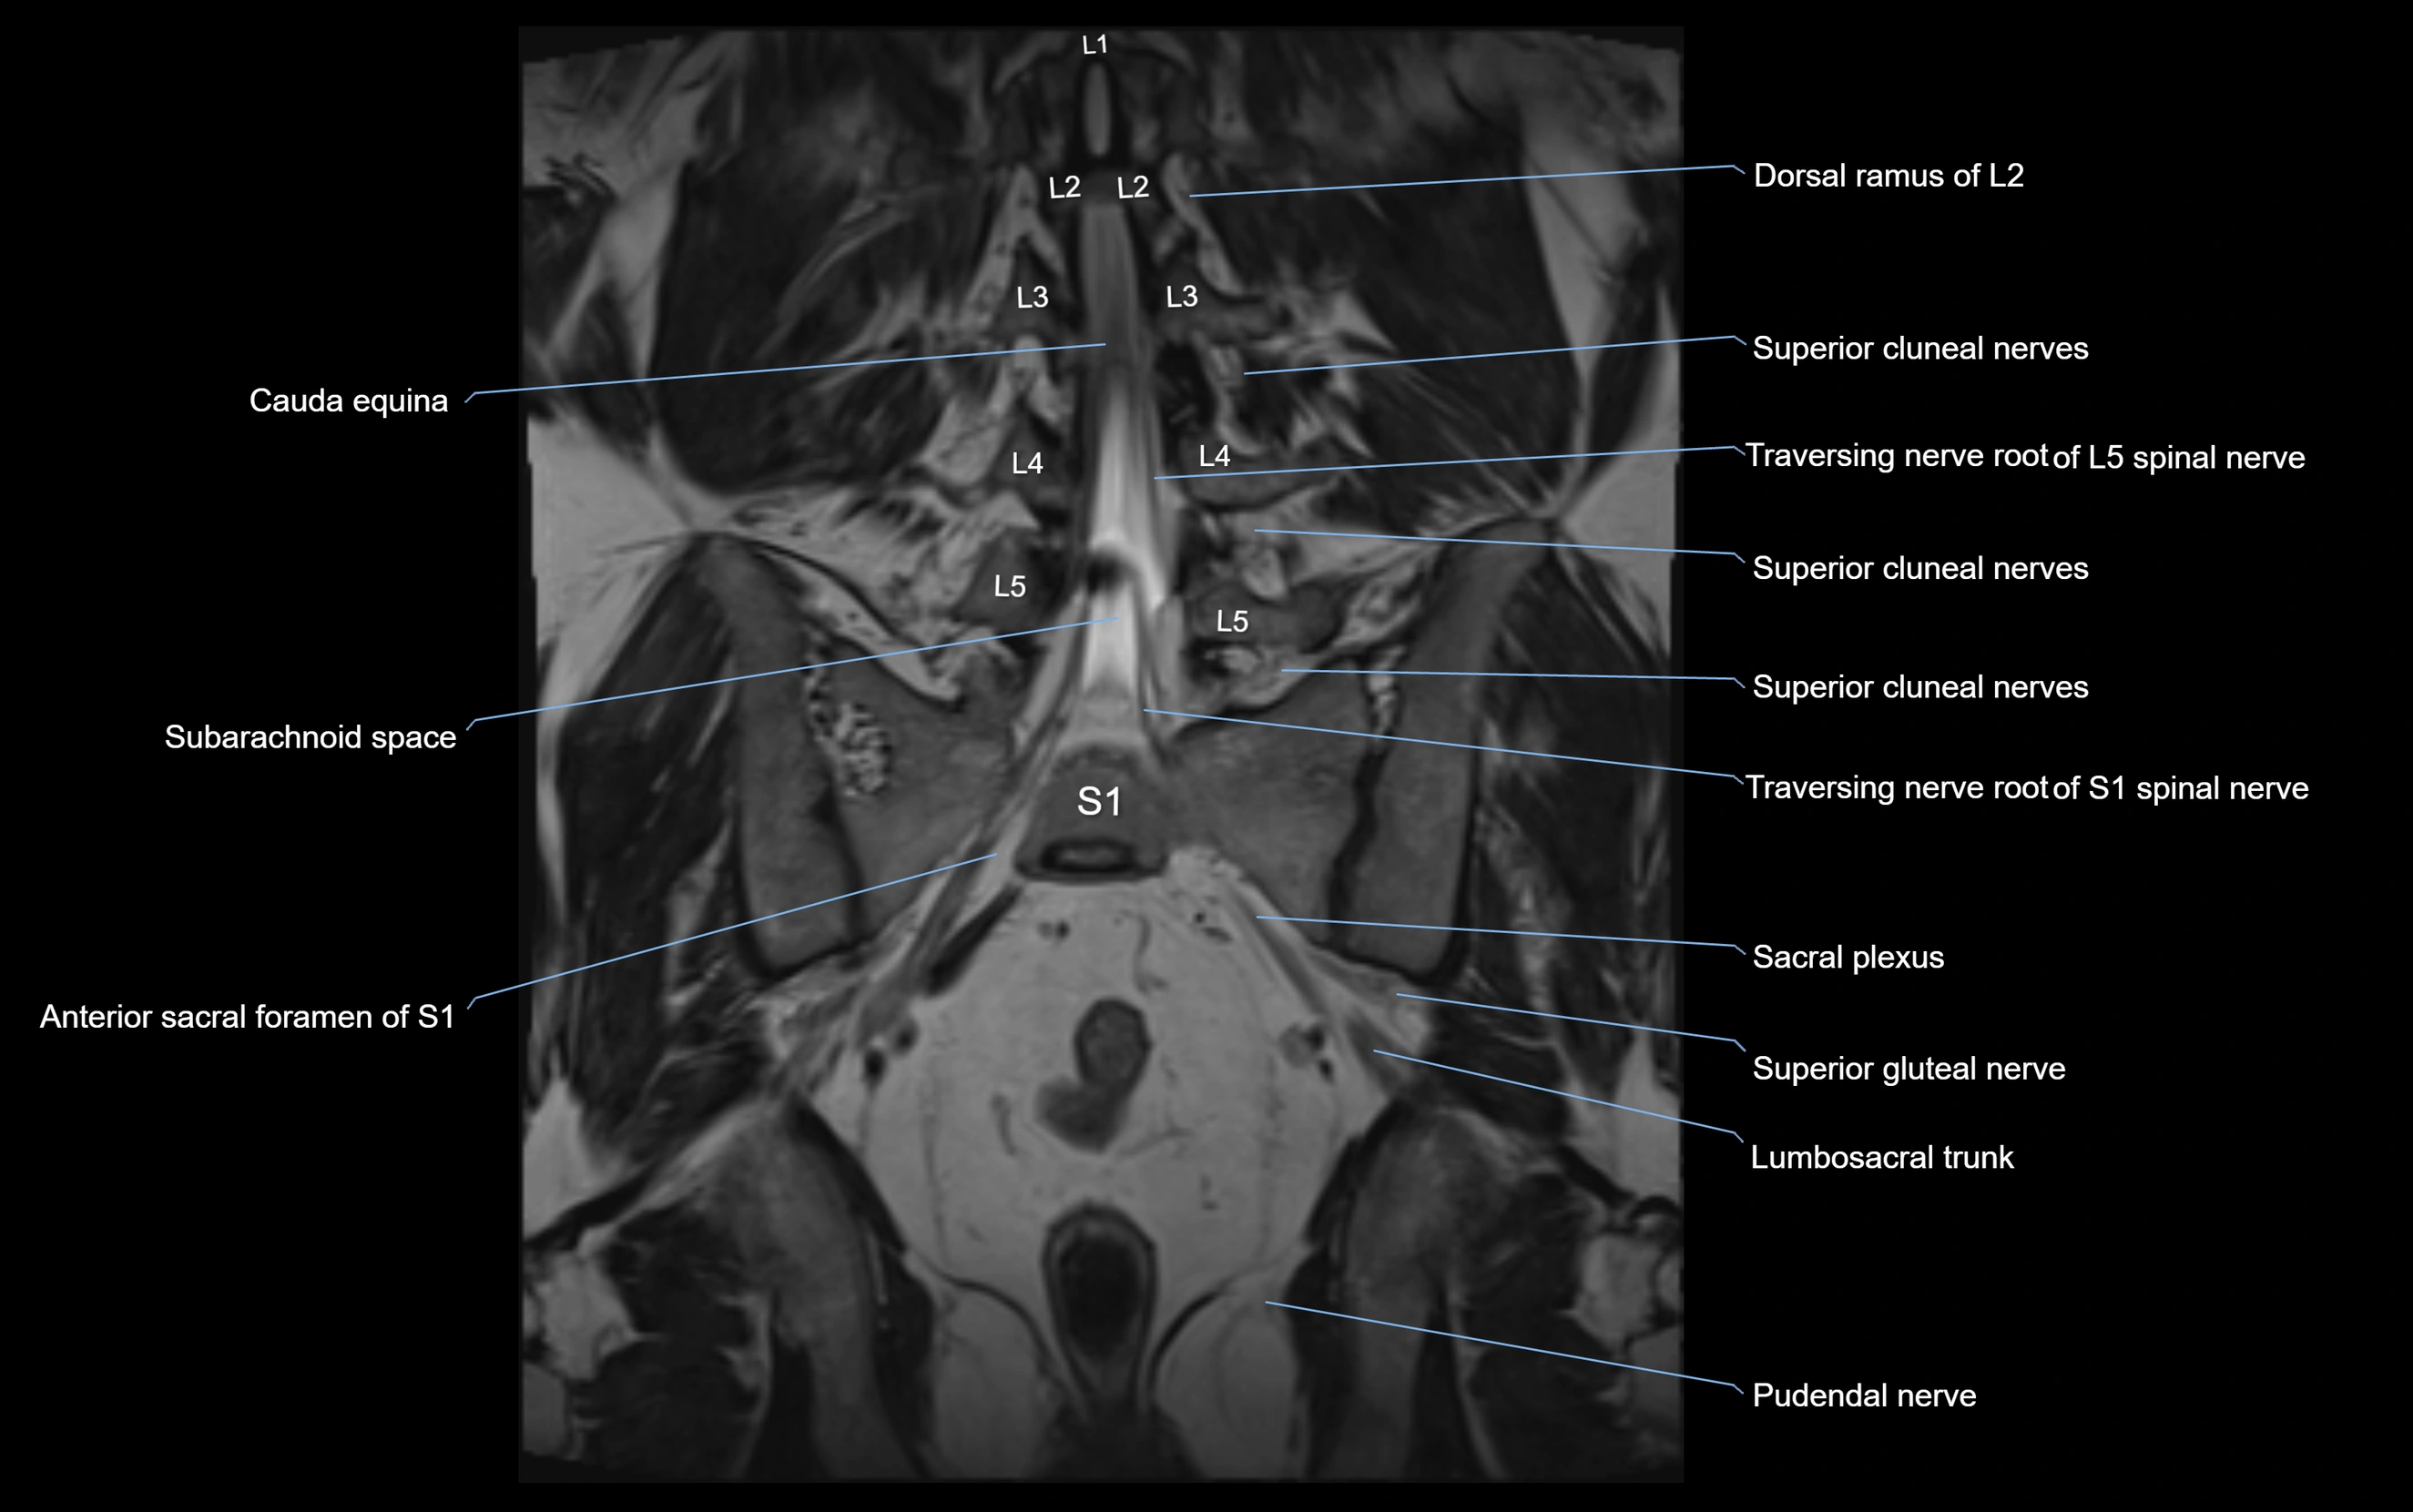

MRI image

image